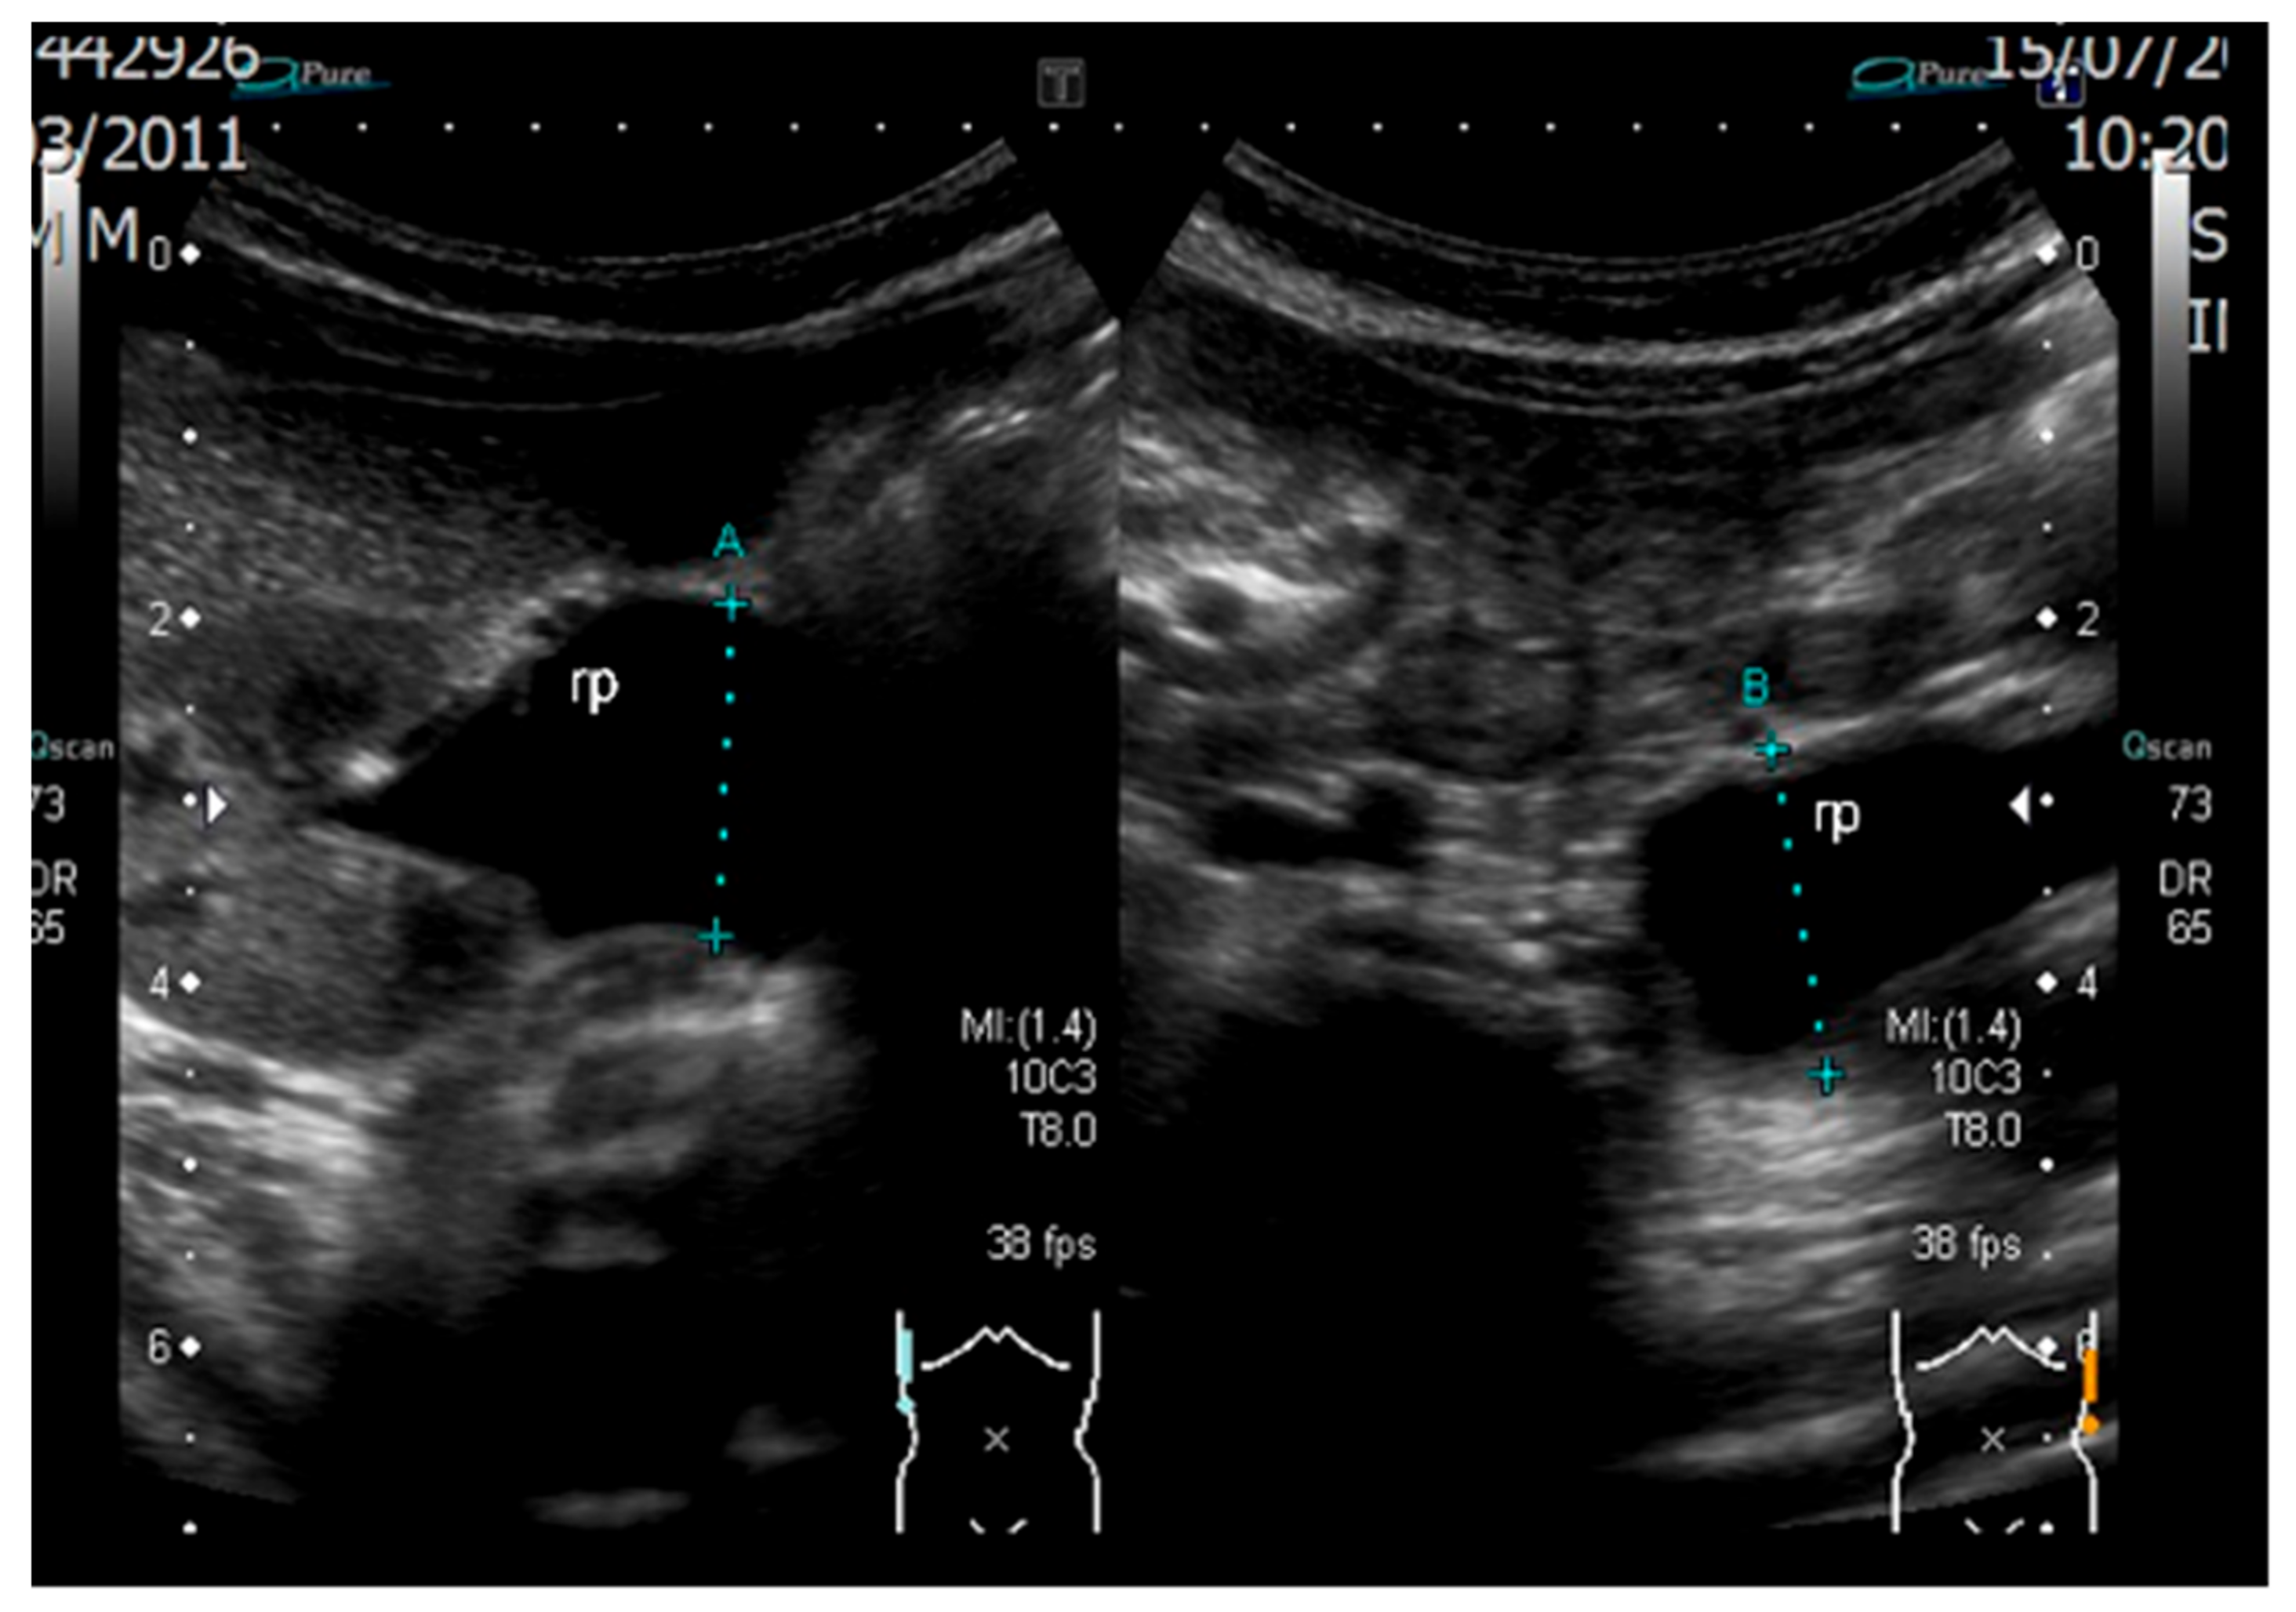

2. Case Report